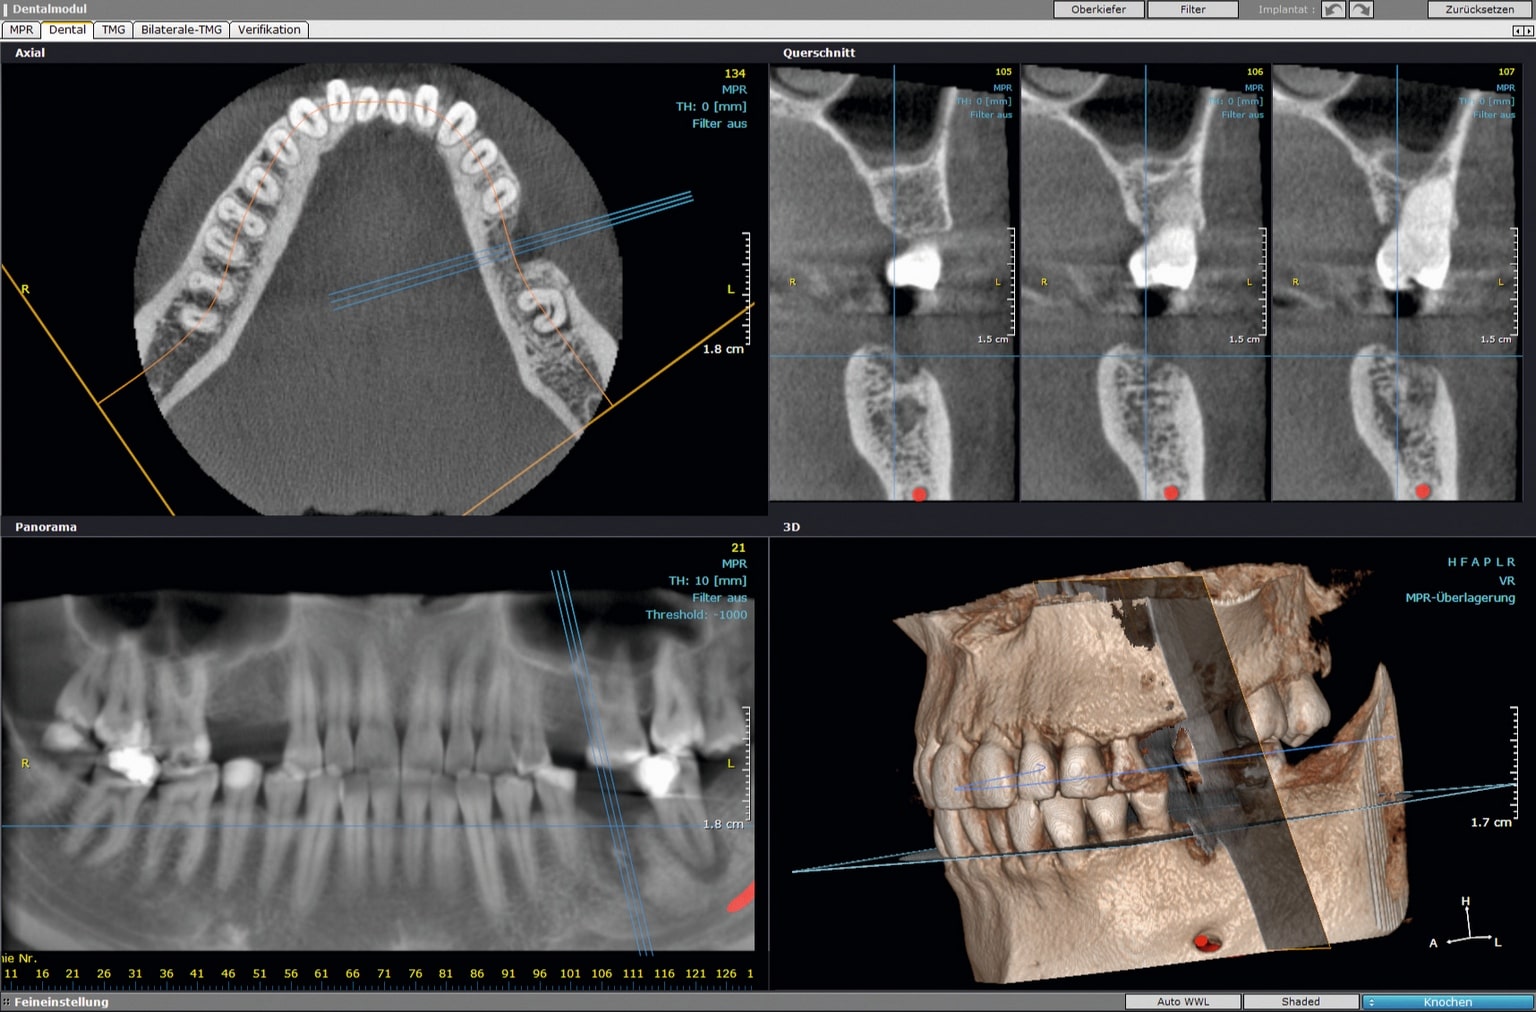

CBCT se koristi za detaljnu dijagnozu stanja čeljusti i okolnih struktura prije protetskih zahvata.

CBCT se koristi za detaljnu dijagnozu stanja čeljusti i okolnih struktura prije protetskih zahvata.